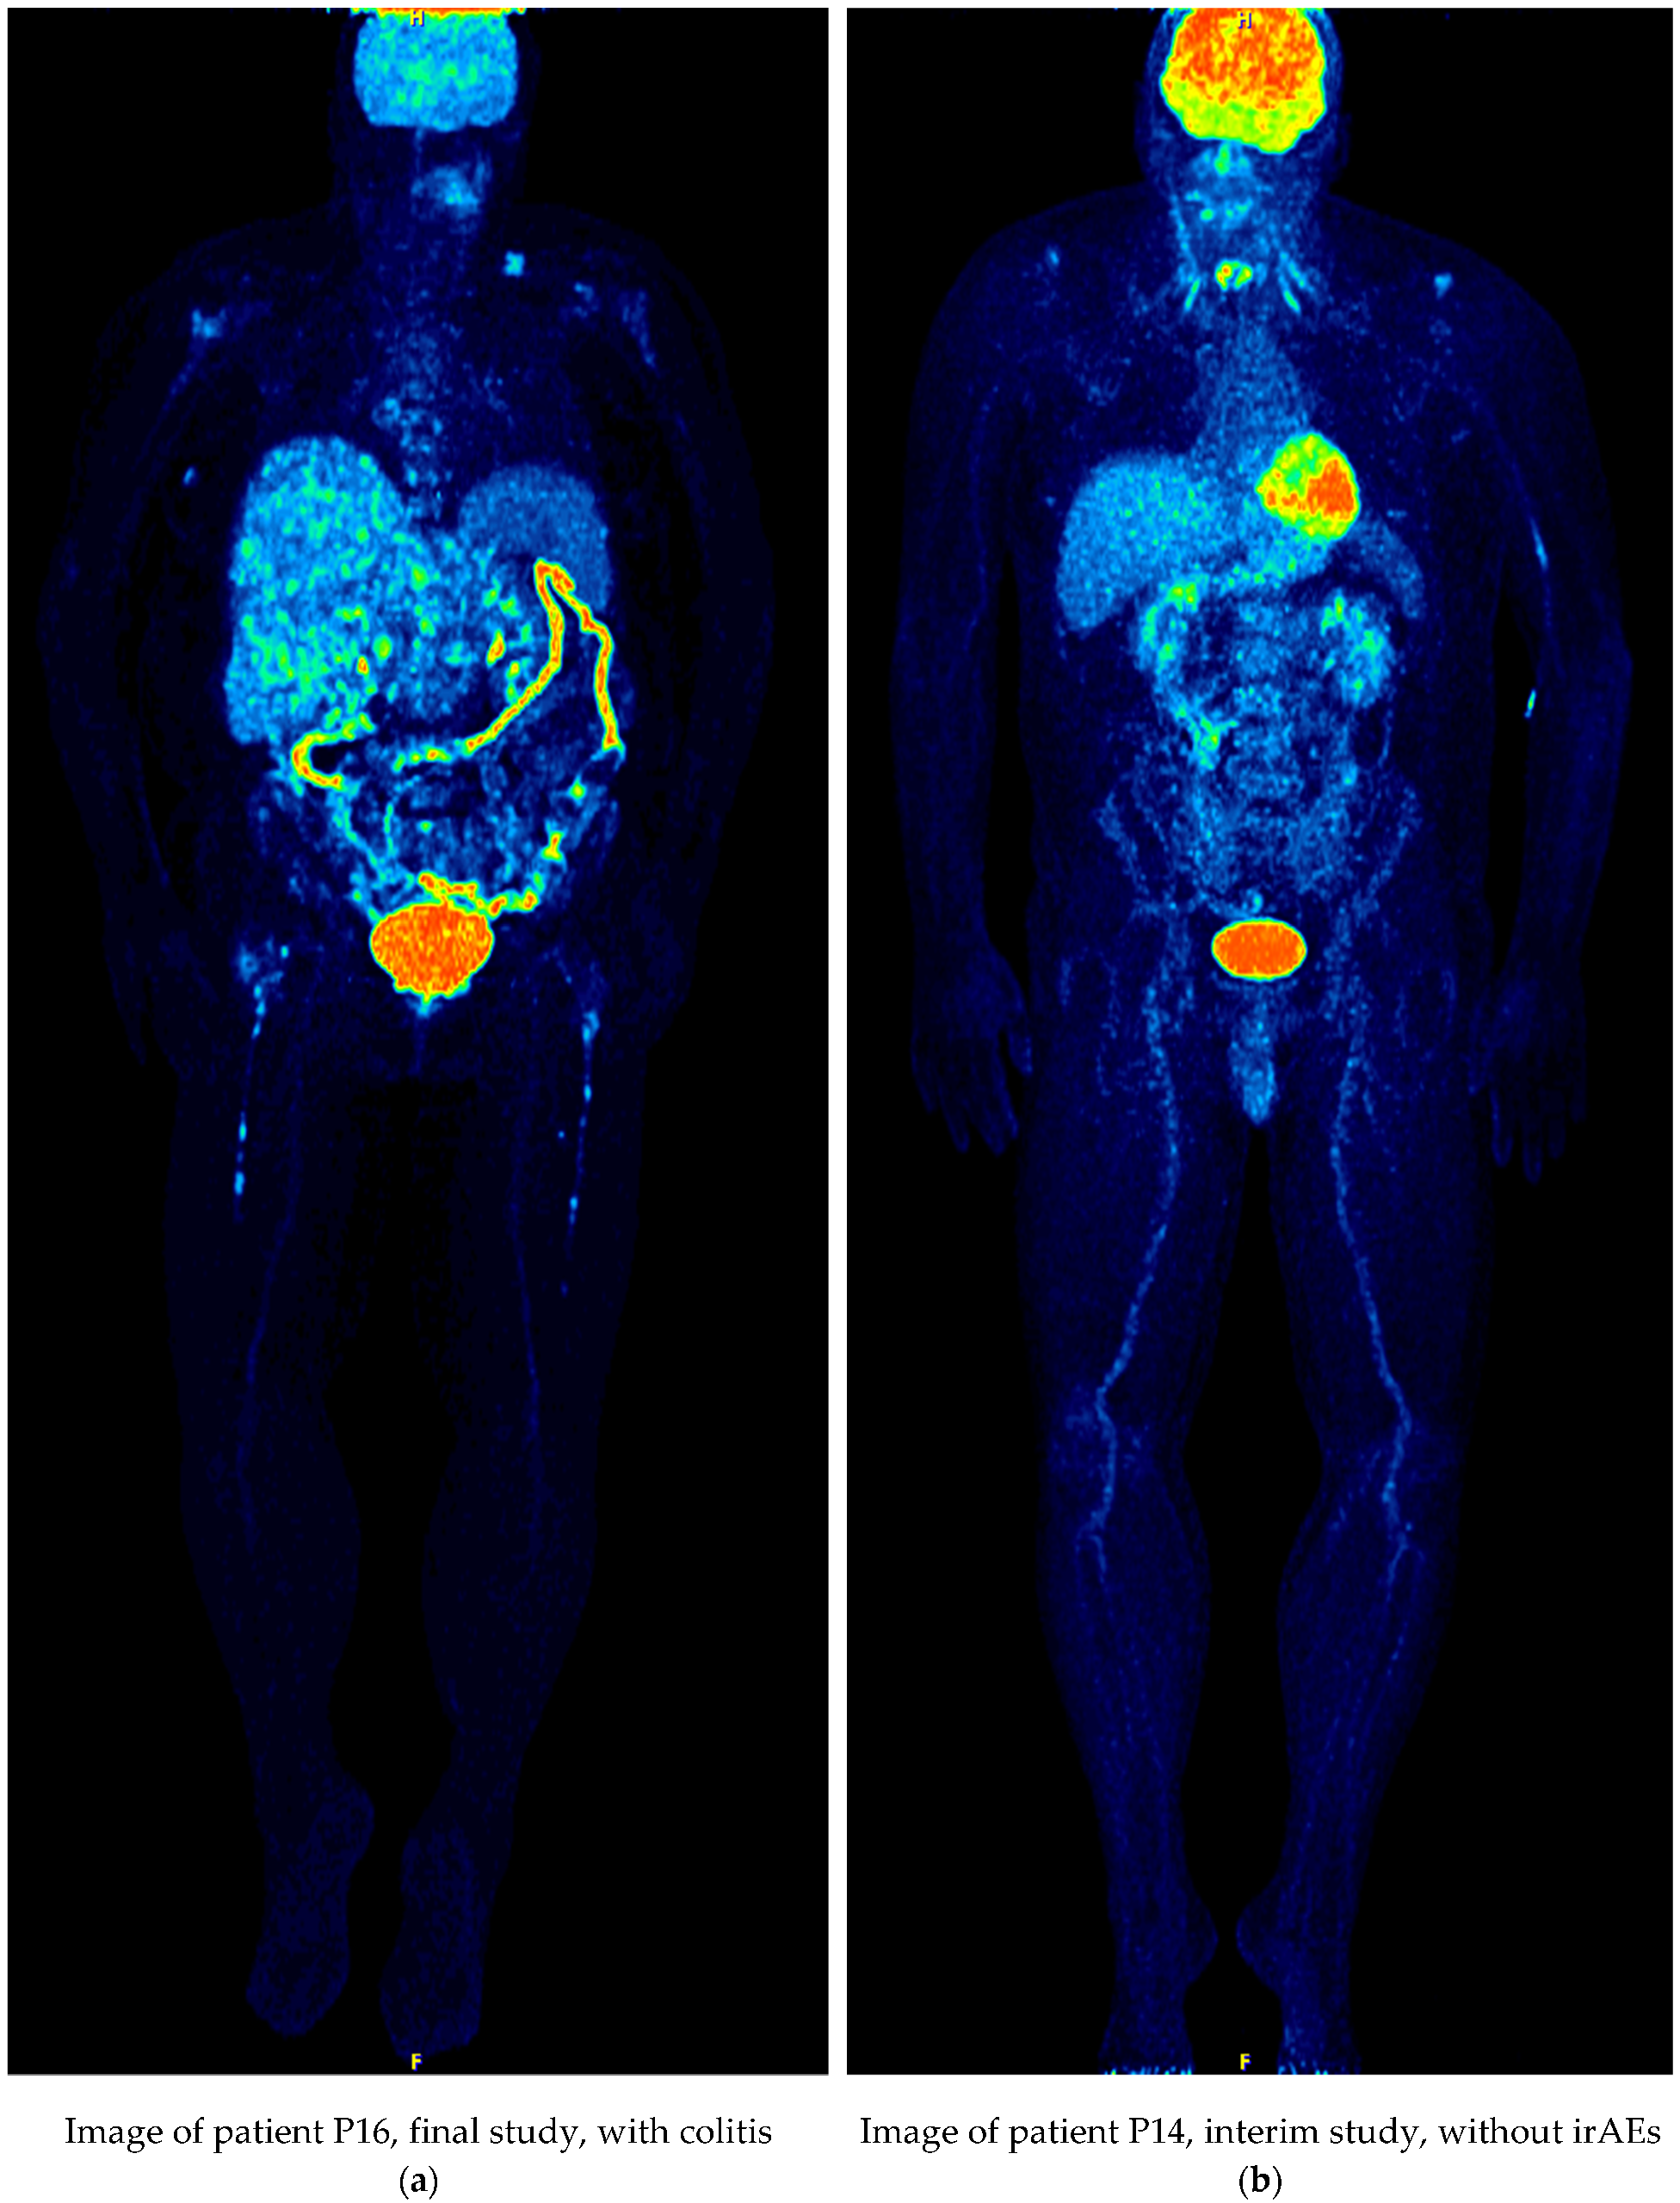

| P16 | 71/F | Baseline | Ipilimumab/Nivolumab | colon uptake | |

| Interim | colitis, sarcoid-like mediastinal lymphadenopathy | PMD | |||

| Final | colitis | PMD | |||

| P16 | Baseline | 2.398 | colon uptake | ||

| Interim | 2.511 | colitis, sarcoid-like mediastinal lymphadenopathy | PMD | NO | |

| Final | 2.574 | colitis | PMD | NO | |

| P16 | Baseline | 2.155 | colon uptake | ||

| Interim | 2.261/0.106 | colitis, sarcoid-like mediastinal lymphadenopathy | PMD | NO | |

| Final | 2.378/0.223 | colitis | PMD | NO | |

| P14 | 52/M | Baseline | Pembrolizumab | laryngeal uptake | |

| Interim | laryngeal uptake | PMR | |||

| Final | laryngeal uptake, radiopharmaceutical uptake in the injection site | PMR | |||

| P14 | Baseline | 2.554 | laryngeal uptake | ||

| Interim | 2.518 | laryngeal uptake | PMR | NO | |

| Final | 2.557 | laryngeal uptake, radiopharmaceutical uptake in the injection site | PMR | YES | |

| P14 | Baseline | 2.302 | laryngeal uptake | ||

| Interim | 2.511/0.209 | laryngeal uptake | PMR | YES | |

| Final | 2.310/0.008 | laryngeal uptake, radiopharmaceutical uptake in the injection site | PMR | YES | |